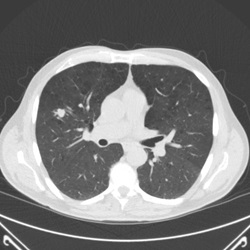

The gold standard for identifying lung cancer early uses computed tomography (CT) scans. Henry Ford Health was part of a national study that found CT lung screening reduced the chance of dying from lung cancer by 20 percent, compared with chest X-ray screening.

The CT scan is quick and painless. It uses a combination of X-rays and computer technology to create detailed images. You don’t have to worry about receiving too much radiation during screening. Our low-dose CT scan technology means you’ll experience about a quarter of the radiation emitted by standard CT scans.